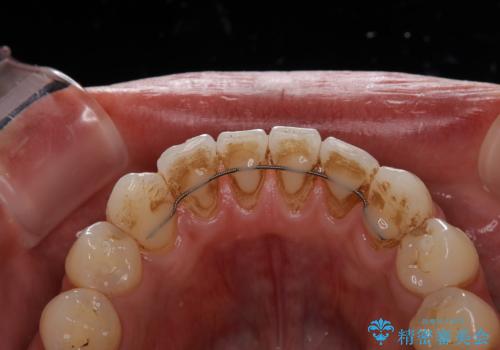

- コーヒーを毎日飲むため、歯が黒くなり気になるとのことでした。

また、以前他院にて矯正治療を行い、前歯の裏側には保定装置がついていることで磨きにくいため機械的に細かい部分のクリーニングも希望とのことでした。

エアフローワンは、特殊なパウダーを混ぜた水を水面にジェット噴射することでバイオフィルム(プラーク)・ステイン(着色)・早期歯石を天然歯やインプラント周囲から除去することが可能な歯面清掃器具です。

従来の荒い研磨剤などを用いた歯面への負担が大きいクリーニングとは異なり、歯質の負担を最小限にした歯面清掃と歯周ポケット内のメンテナンスを行えます。